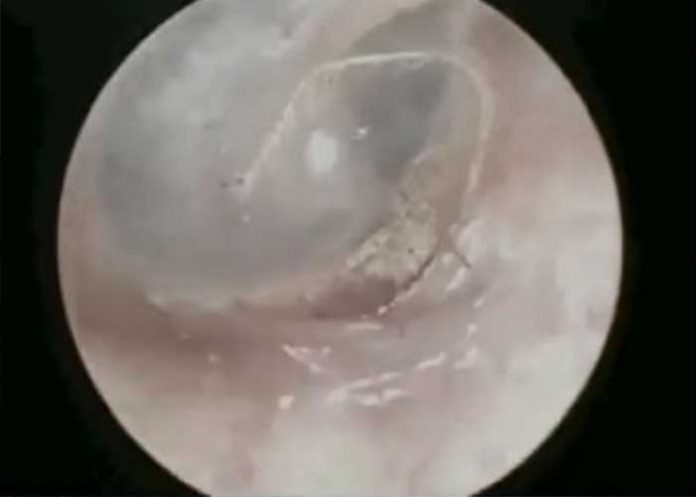

Recientemente se reportó un insólito caso en el país asiático donde, un hombre de 20 años de edad, tenía horrible araña dentro de su oído, pero lo más insólito es que el animal estaba tejiendo su telaraña dentro del oído del chico.

Ya con un médico, y usando un endoscopio, encontraron a la araña en su oído.

El aterrador momento quedó grabado en video, posteriormente fue subido a redes sociales donde se volvió viral rápidamente.

El médico comentó que tuvo que verter agua sobre el hombre para poder retirar al bicho.